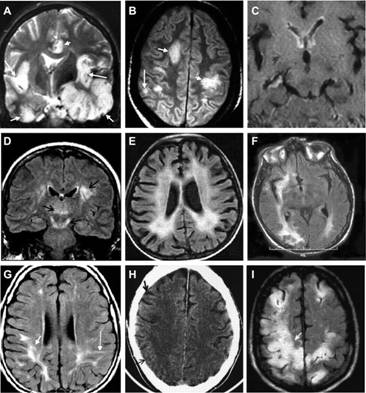

Hình ảnh học

Thực hiện đầu tiên khi nghi ngờ viêm não.

Cung cấp thông tin đánh giá nhiễm trùng hệ thần kinh TW nhưng thường không đặc hiệu. Phát hiện sau khởi phát triệu chứng 2-4 ngày.

MRI nhạy hơn CT trong việc phát hiện sớm những sang thương trên não do HSE (Neurologist 2000;6:145–59.)

Tổn thương gợi ý chẩn đoán: T1 giảm và T2 tăng ở chất xám thuỳ thái dương trong và thuỳ trán ổ mắt, có thể có xuất huyết kèm theo, thường không đối xứng. Ngoài ra tổn thương có thể lan đến thuỳ đảo và hồi góc, có thể bắt Gado màng não và các hồi não.

MRI bình thường trong khoảng 10% BN HSV-PCR (+). Nhưng số còn lại đều có tổn thương thuỳ thái dương (90%)